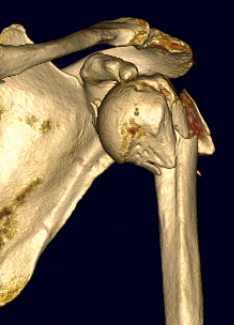

Four part